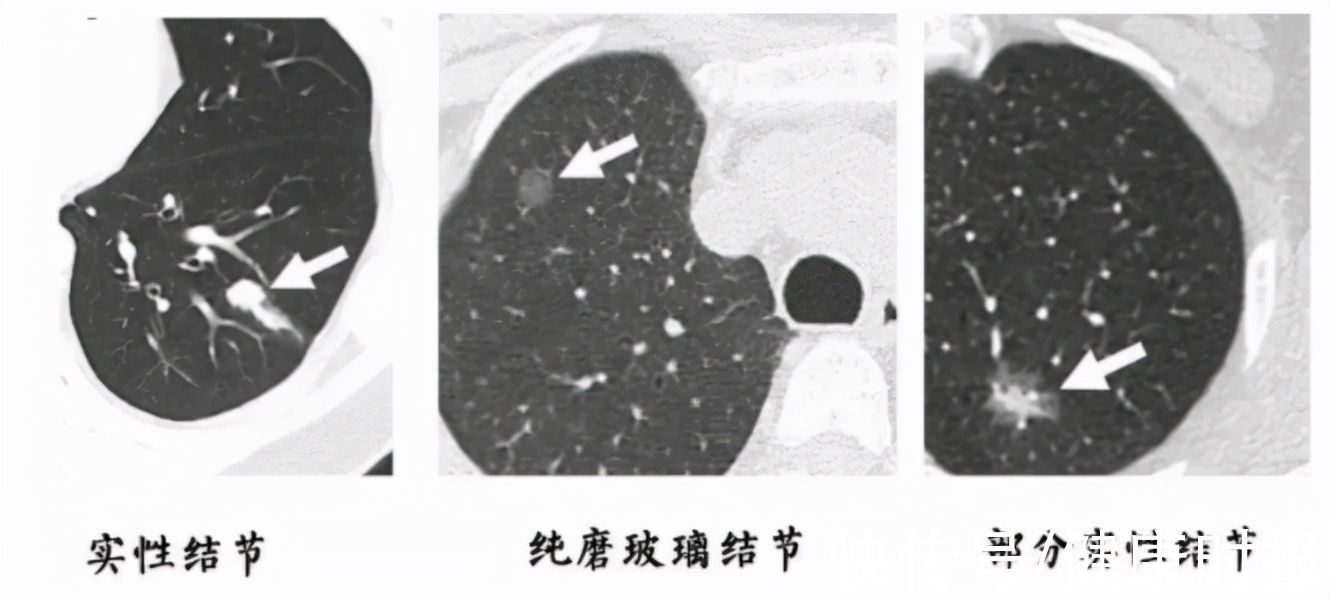

结节一般是指在CT、彩超、磁共振等检查中发现的直径小于3厘米的病灶。

医生会根据结节的形状、密度、血液供应等特点,来初步判断这些结节的性质。

虽然多数的结节为良性,但也有些结节是恶性肿瘤的前期表现,一旦检出,应该密切复查,及时干预治疗。